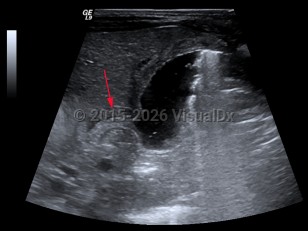

Hypertrophic pyloric stenosis

Hypertrophic pyloric stenosis (PS) is a narrowing of the pyloric lumen due to tissue hypertrophy and scarring. The resultant intestinal narrowing leads to gastric outlet obstruction and bowel obstruction. Although hypertrophic PS can very rarely occur in children and adults, this summary is focused on infantile hypertrophic PS. Patients present with emesis, usually within the first several months of life.

PS is predominantly seen in males (approximately 4:1) and presents typically at 2-7 weeks of life with nonbilious, postprandial projectile emesis and dehydration. Children of parents who had PS have a 20% increased risk of developing PS, suggesting a genetic component, although no clear genetic etiology has been identified.

The complications of PS are due to dehydration and malnutrition. Patients often present with lethargy, failure to thrive, and a hypochloremic, hypokalemic metabolic alkalosis.

Symptoms will continue until a corrective pyloromyotomy is performed.